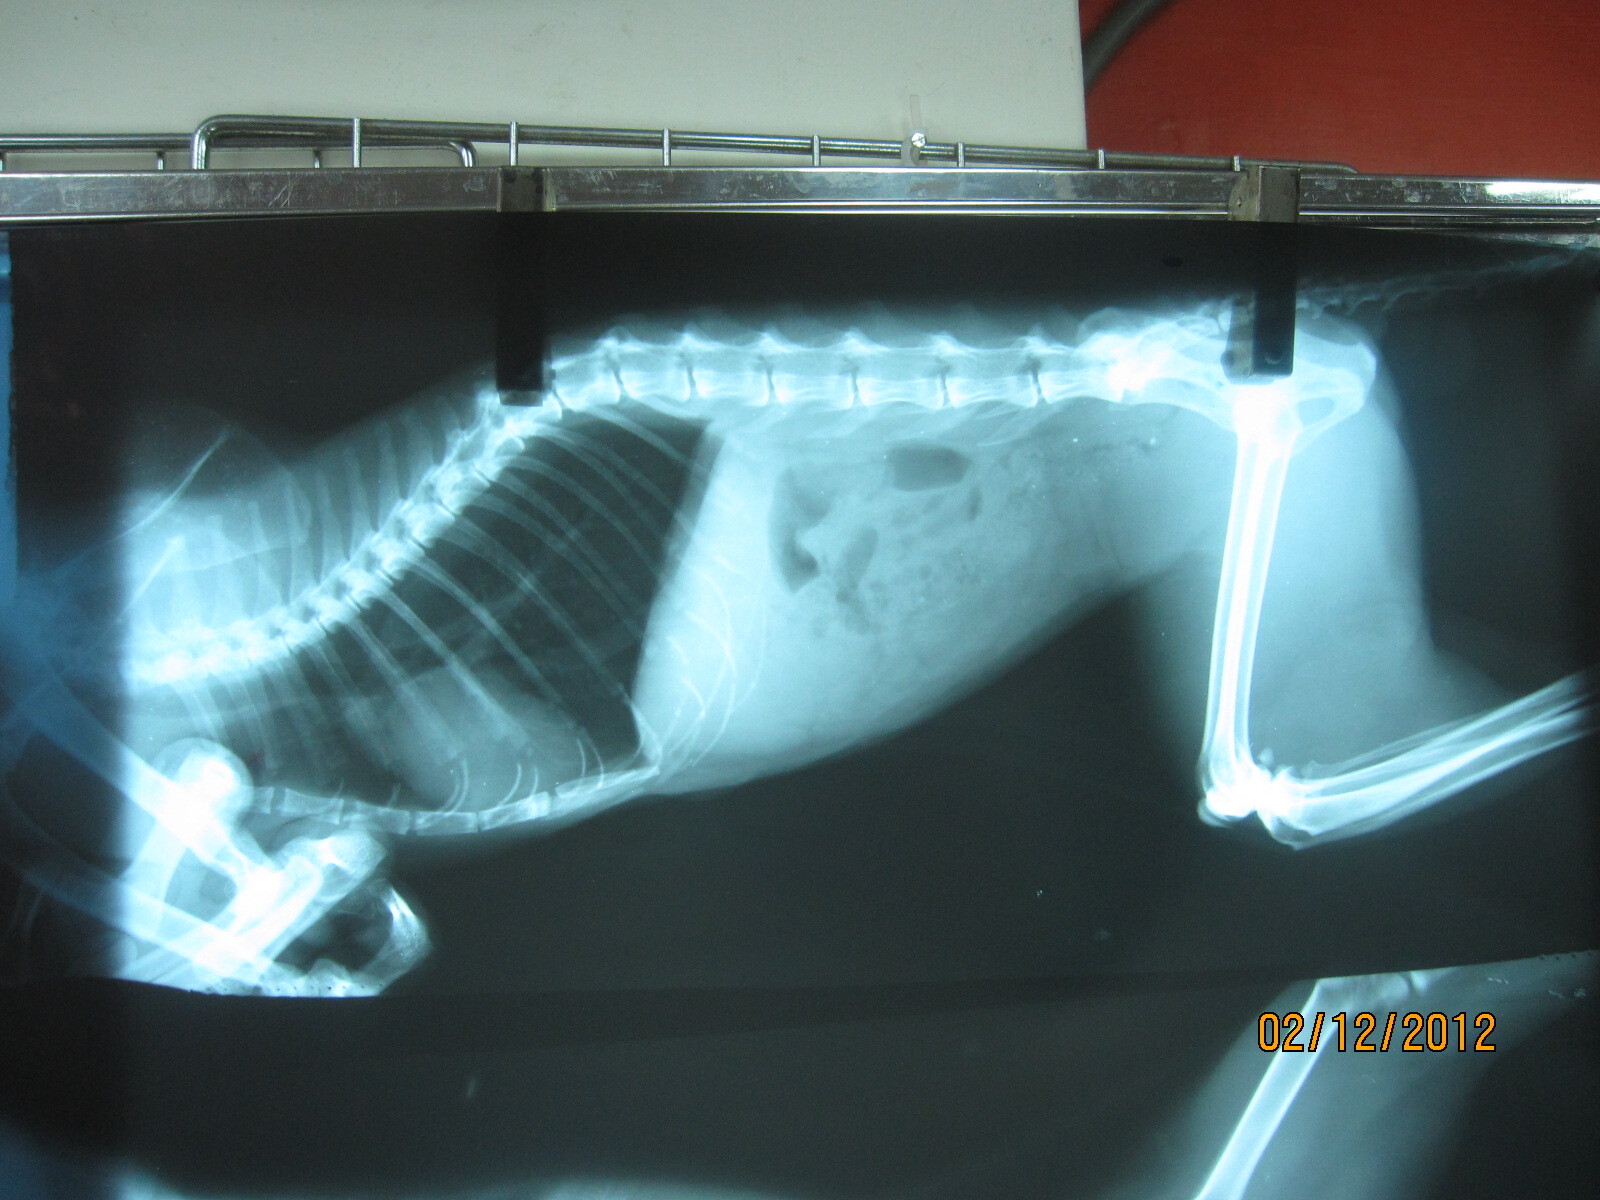

主題: 周明德在北海岸救回的重病母貓 申請者姓名: 楊雅筑 花色: 申請日期: 2012-02-22 17:45:55 申請者部落格: 申請者臉書網址: 所在縣市/合作醫院: 新北市/集賢愛生 治療費用: 9300元 需求人數: 10人 已結案 (2012-03-14 16:00:00) 報名人員: Daisy Kaimin Tu(已付款)、冥王星獅子(已付款)、張競文(已付款)、貓老大(已付款)、Ariel Yu-Ting Tu(已付款)、Shirley(已付款)、蕭小英(已付款)、范立縈(已付款)、Wallysam(已付款)、嘟嘟(已付款)、 候補人員: 動物病情說明: 這隻虎班母是周明德在北海岸救回的病貓,當時牠在一個空曠的停車場,没有遮蔽物,無法行走,送醫之後不吃,莫名一直叫,醫生懷疑是結紮没有處理好,又腎臟有大小顆

決定動開腹探測手術,一開刀,原來一直叫假發情是甲狀腺亢進,腎臟一顆委縮到像蠶豆小,一顆是正常的一半大,大腸網膜感染嚴重,把腸子全部清洗完全,現在都已處理好,住院休養中,貓咪後續會找人收留,因為腎臟病的貓咪不能野放,要細心照顧